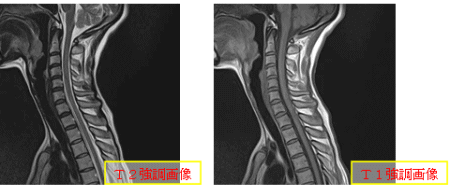

通常のMRI検査

MRI検査は、撮影する条件によって画像のコントラストが違います。これらを数パターン撮影することにより診断します。撮影部位によって2~3パターンをいろいろな角度で切断した画像を撮影するので時間がかかります。20~30分くらいです。また、造影剤を使用する場合、使用前と使用後の撮影があり、更に検査時間は10~15分くらい長くなります。